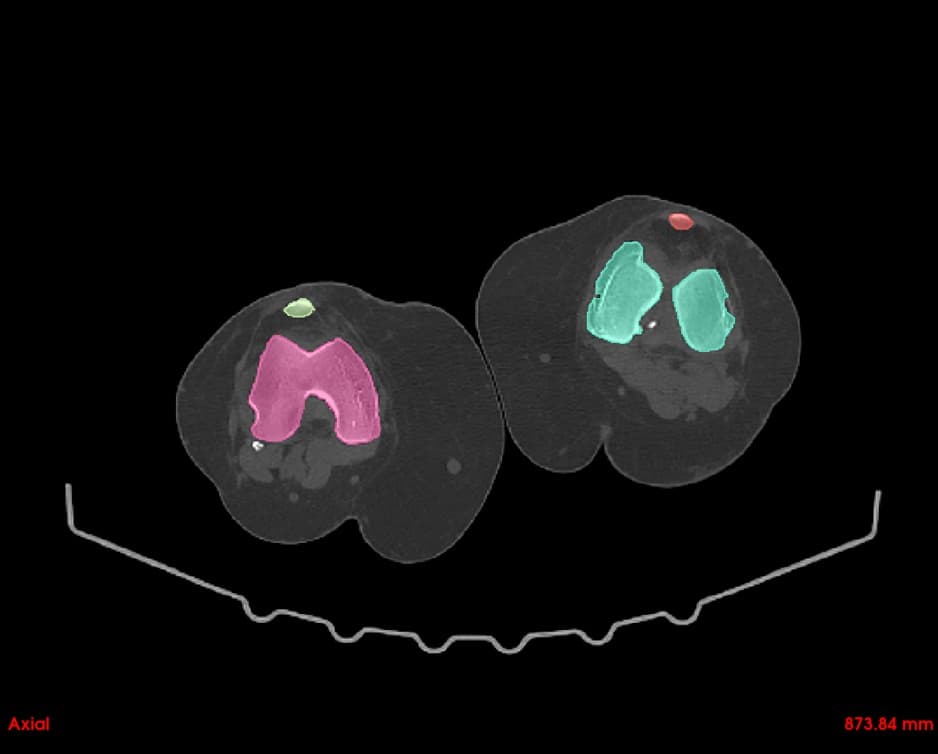

User-friendly interface with precise editing capabilities for bones, vasculature, and soft tissues. Rapidly create patient-specific anatomical models.

Segment bones, vasculature, and soft tissues with precision. User-friendly tools for accurate anatomical boundary delineation.

Simultaneous axial, sagittal, and coronal views. Navigate through slices with synchronized cross-referencing.